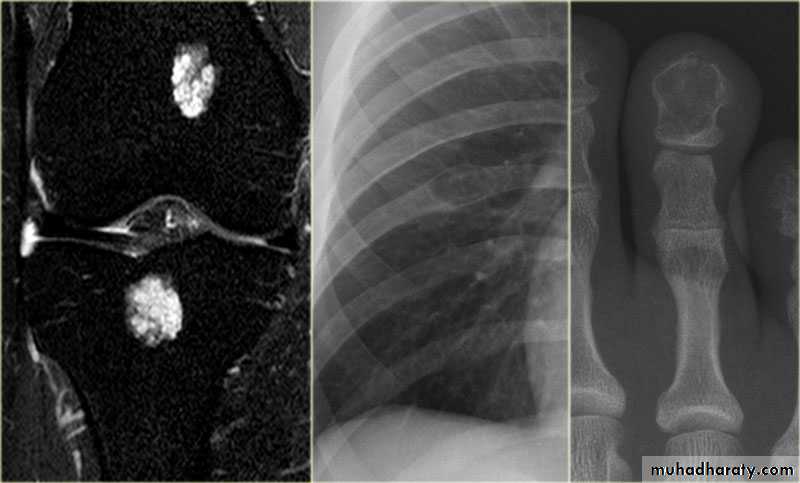

V.MRI (magnetic resonance imaging in bone disease ):

.demonstrate disc herniation and spinal cord or nerve root compression. to diagnose bone metastasis

.show extent of primary bone tumor & demonstrate myloma & lymphoma

. image soft tissue mass

Giant cell tumour

Enchondromas :Fibrous cortical defects ( non ossifying fibromas )

Fibrous dysplasia :